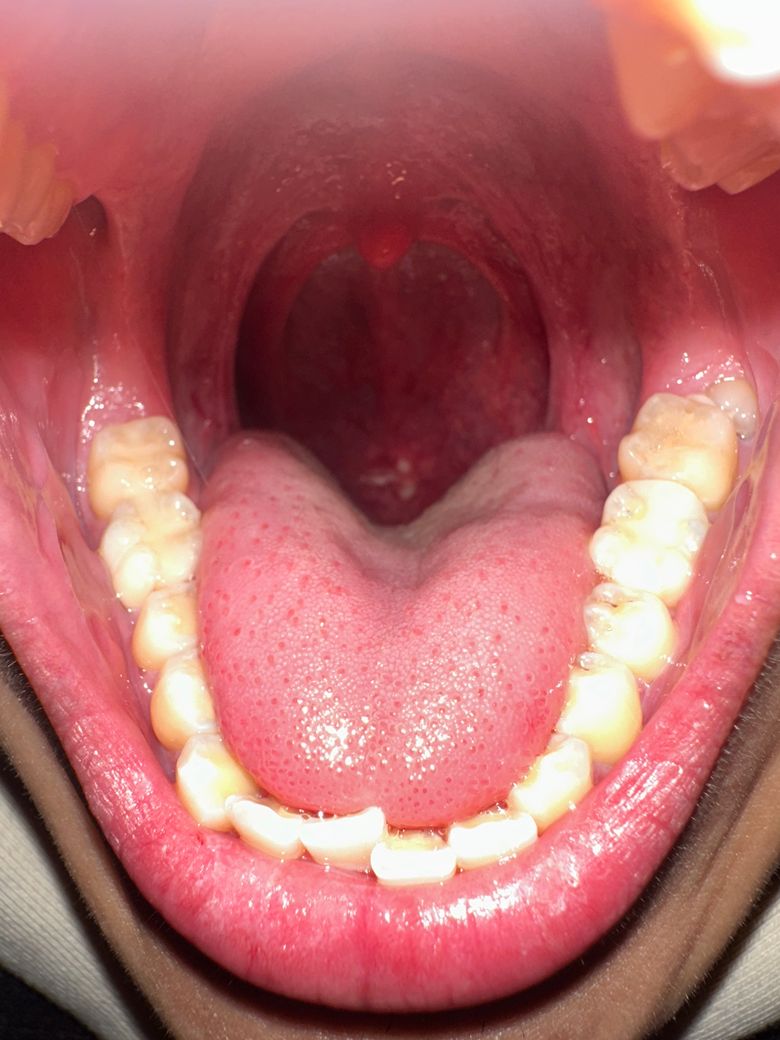

목에 이거 뭔지 좀 알려주세요 ㅠㅠ 제가 목이 막히는 느낌이 들고 이물감 있고 따갑고 아팠는데 약 먹니니까 조금은 괜찮아졌습니다.. 근데 지난주부터 보니까 입 안쪽에 처음에는 구내염처럼 보였는데 오늘 보니까 갑자기 저렇게 하얀색으로 뭐가 덮어져 있습니다.. 저게 혹시 뭔지 알수있을까여?? ㅠㅠ 낼 내과는 가보려고 하는데 사진 있습니다 제가 어제까지 먹었던 약들입니더

사진으로는 정확한 진단 불가능하며 병원 방문하셔서 직접 육안으로 진료 보셔야 합니다

정확한 원인 파악을 위해선 이비인후과나 치과에서 진료를 받으셔야 하고 원인에 맞는 치료를 받는 것이 좋습니다